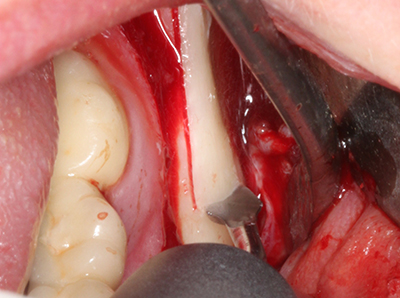

Bei der Knochenblockentnahme zeigen sich weitere Vorteile für die Piezochirurgie: Neben der bereits beschriebenen hohen Präzision bei der Osteotomie stellt sich gerade die Verwendung der dünnen Sägespitzen als besonders materialschonend heraus. Bei der Verwendung insbesondere von Lindemannfräsen sind mit deutlich höheren Entnahmeverlusten durch die dickere Instrumentenspitze zu rechnen (Lakshmiganthan, Gokulanathan et al. 2012). Die insbesondere bei retromolar entnommenen Blocktransplantaten notwendige basale Abtrennung wird durch speziell hierfür vorgesehene rechtwinklige Sägen erleichtert, so dass die Piezochirurgie als präzises, übersichtliches und sicheres Verfahren zur retromolaren Knochenblockgewinnung angesehen wird (Happe 2007) (Abb. 1-12).

Abb. 1: Präparation eines ent-sprechenden Knochendeckels mit dem Piezomed.

Abb. 3: Die basale Abtrennung des Blocks wird durch speziell abgewinkelte Aufsätze erleichtert.